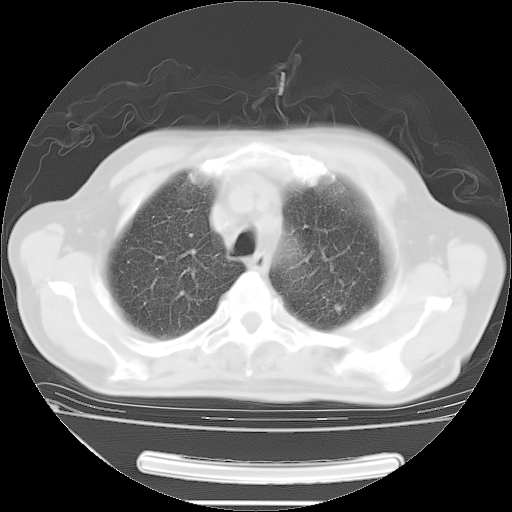

今天复查肺部CT,发现双肺广泛磨玻璃样改变。所以我把3月19日和5月9日相隔50天的肺部CT上传。请大家会诊。

2009年3月19日肺部CT片。

5月9日肺部CT(在4月27日齐鲁医院肺部CT描述部分肺组织磨玻璃样改变,12天后肺组织广泛磨玻璃样改变)